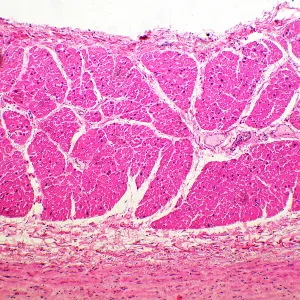

Микроскоп в работе »